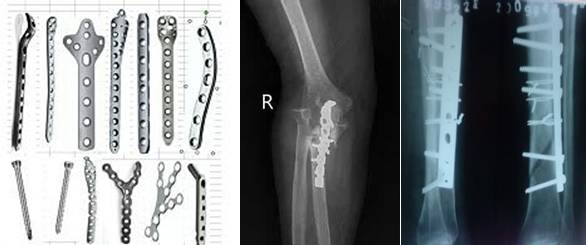

骨科内固定材料

骨科内固定材料主要有不锈钢系列、钴铬钼合金、钛和钛合金等。目前所用的较新的内固定材料多由纯钛或钛合金制成,与磁场没有相互作用,在磁场中不会移动,可以行磁共振检查,但仍可能出现伪影的问题。

而较老的不锈钢等材料的内固定物,由于材料在强大磁场中可能发生移动而损伤邻近大血管和重要组织,产生严重后果,一般是磁共振检查的相对禁忌证。产生伪影的问题,钛金属略微优于不锈钢材质。患者事先一定要和医师充分沟通后才能确定最佳植入材料和最适检查方法。